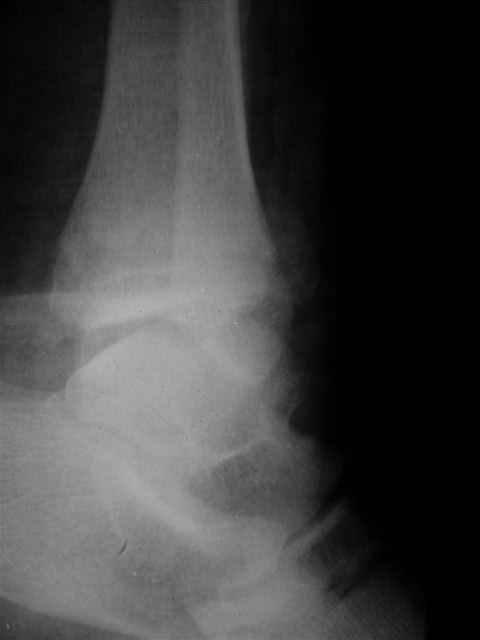

Уважаемый Иван,

Я предупреждал, что ничего сверхъестественного. Каюсь, что одна из спиц прошла несколько дальше, чем нужно было, но главное - перелом стабилизирован и больной работает суставом в полном объёме, несмотря на представленную раннее травму коленного сустава.